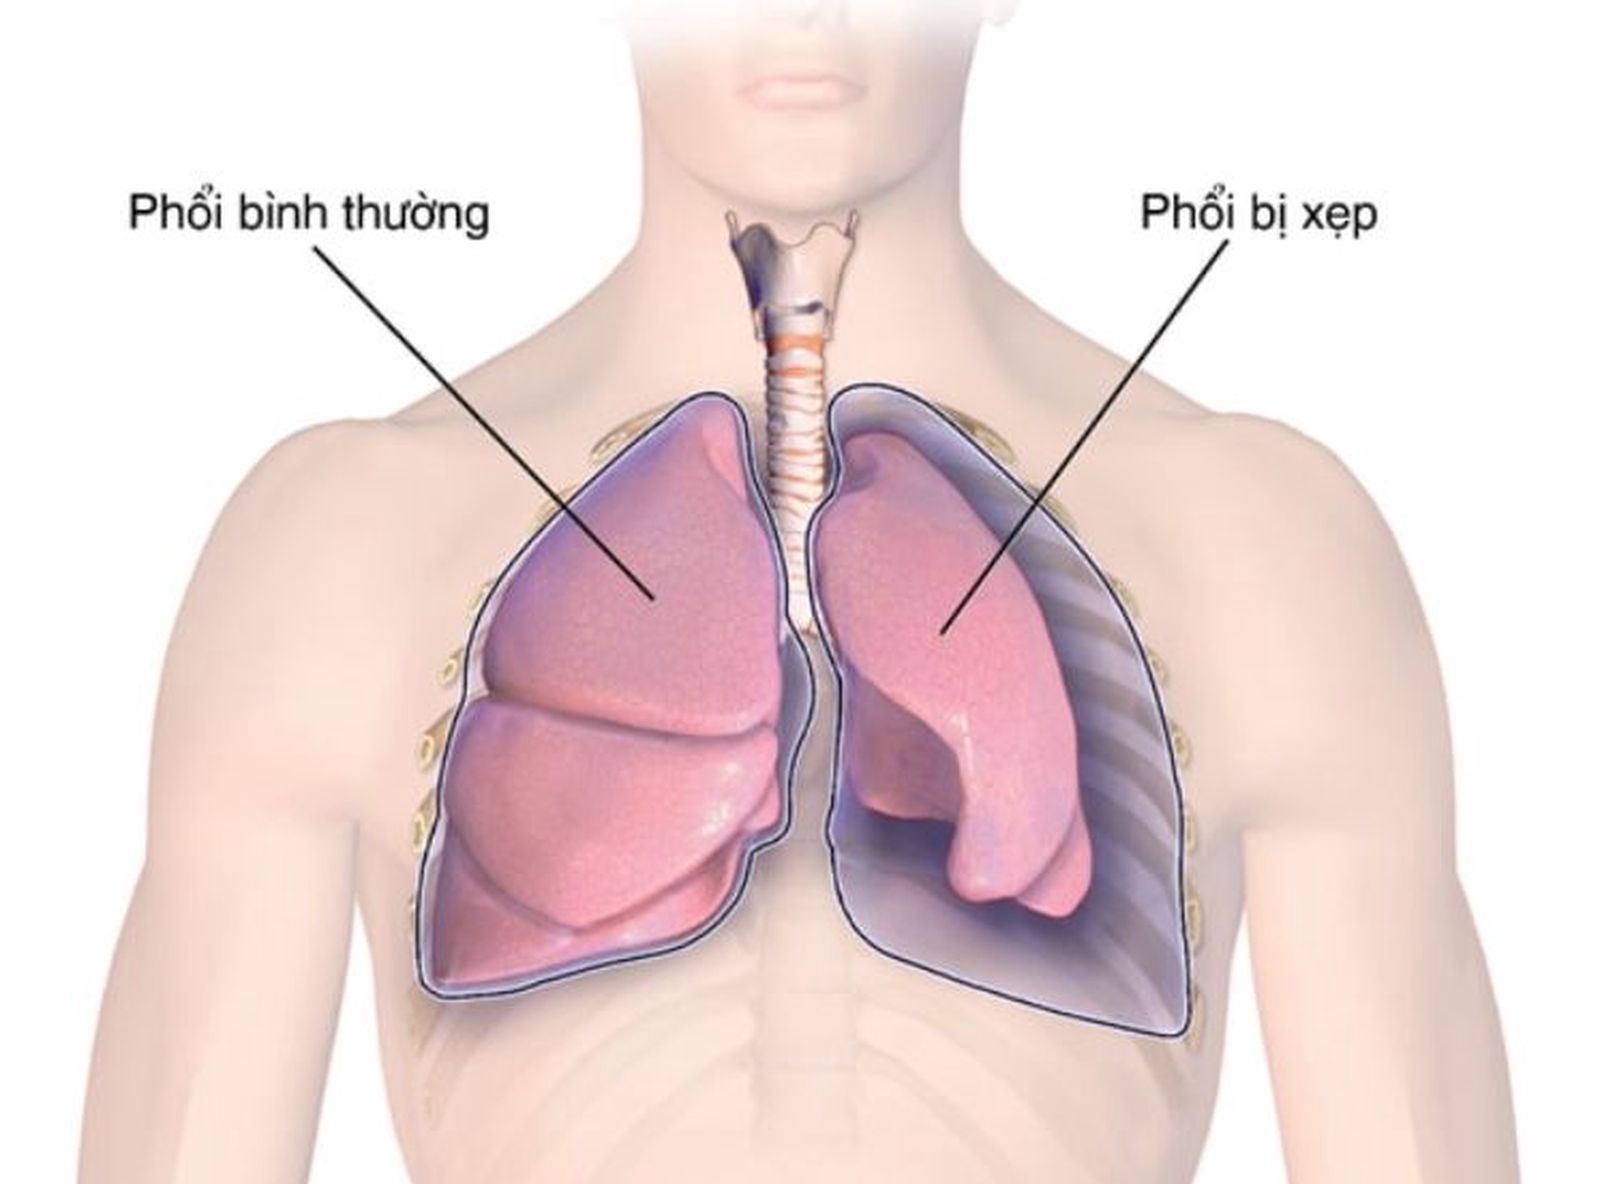

Схемы дыхания: Пневмоторакс на изображениях